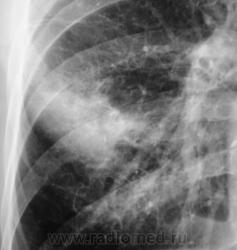

Контроль через 1 месяц после противовоспалительной терапии.